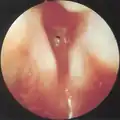

CT scans and MRI (magnetic resonance imaging) can help in diagnosis. X-rays can determine the location and size of the narrowed airway portion. Optical coherence tomography (OCT) can help observe the progression of the injury. Esophageal pH monitoring can help detect any acid reflux, which can worsen the condition. A laryngoscopy or an endoscope can be inserted and used to see the vocal cords, airway, and esophagus/trachea. Spirometry is a useful way to measure respiratory function. People affected by subglottic stenosis have a FEV1 of over 10.[2]

Subglottic stenosis is graded according to the Cotton-Myer classification system from one to four based on the severity of the blockage. Grade 1 is up to 50% obstruction, Grade 2 is 50-70% obstruction, Grade 3 is 70-99% obstruction, and Grade 4 is with no visible lumen.[5]

Grade 1 subglottic stenosis

Grade 2 subglottic stenosis

Grade 3 subglottic stenosis

Grade 4 subglottic stenosis